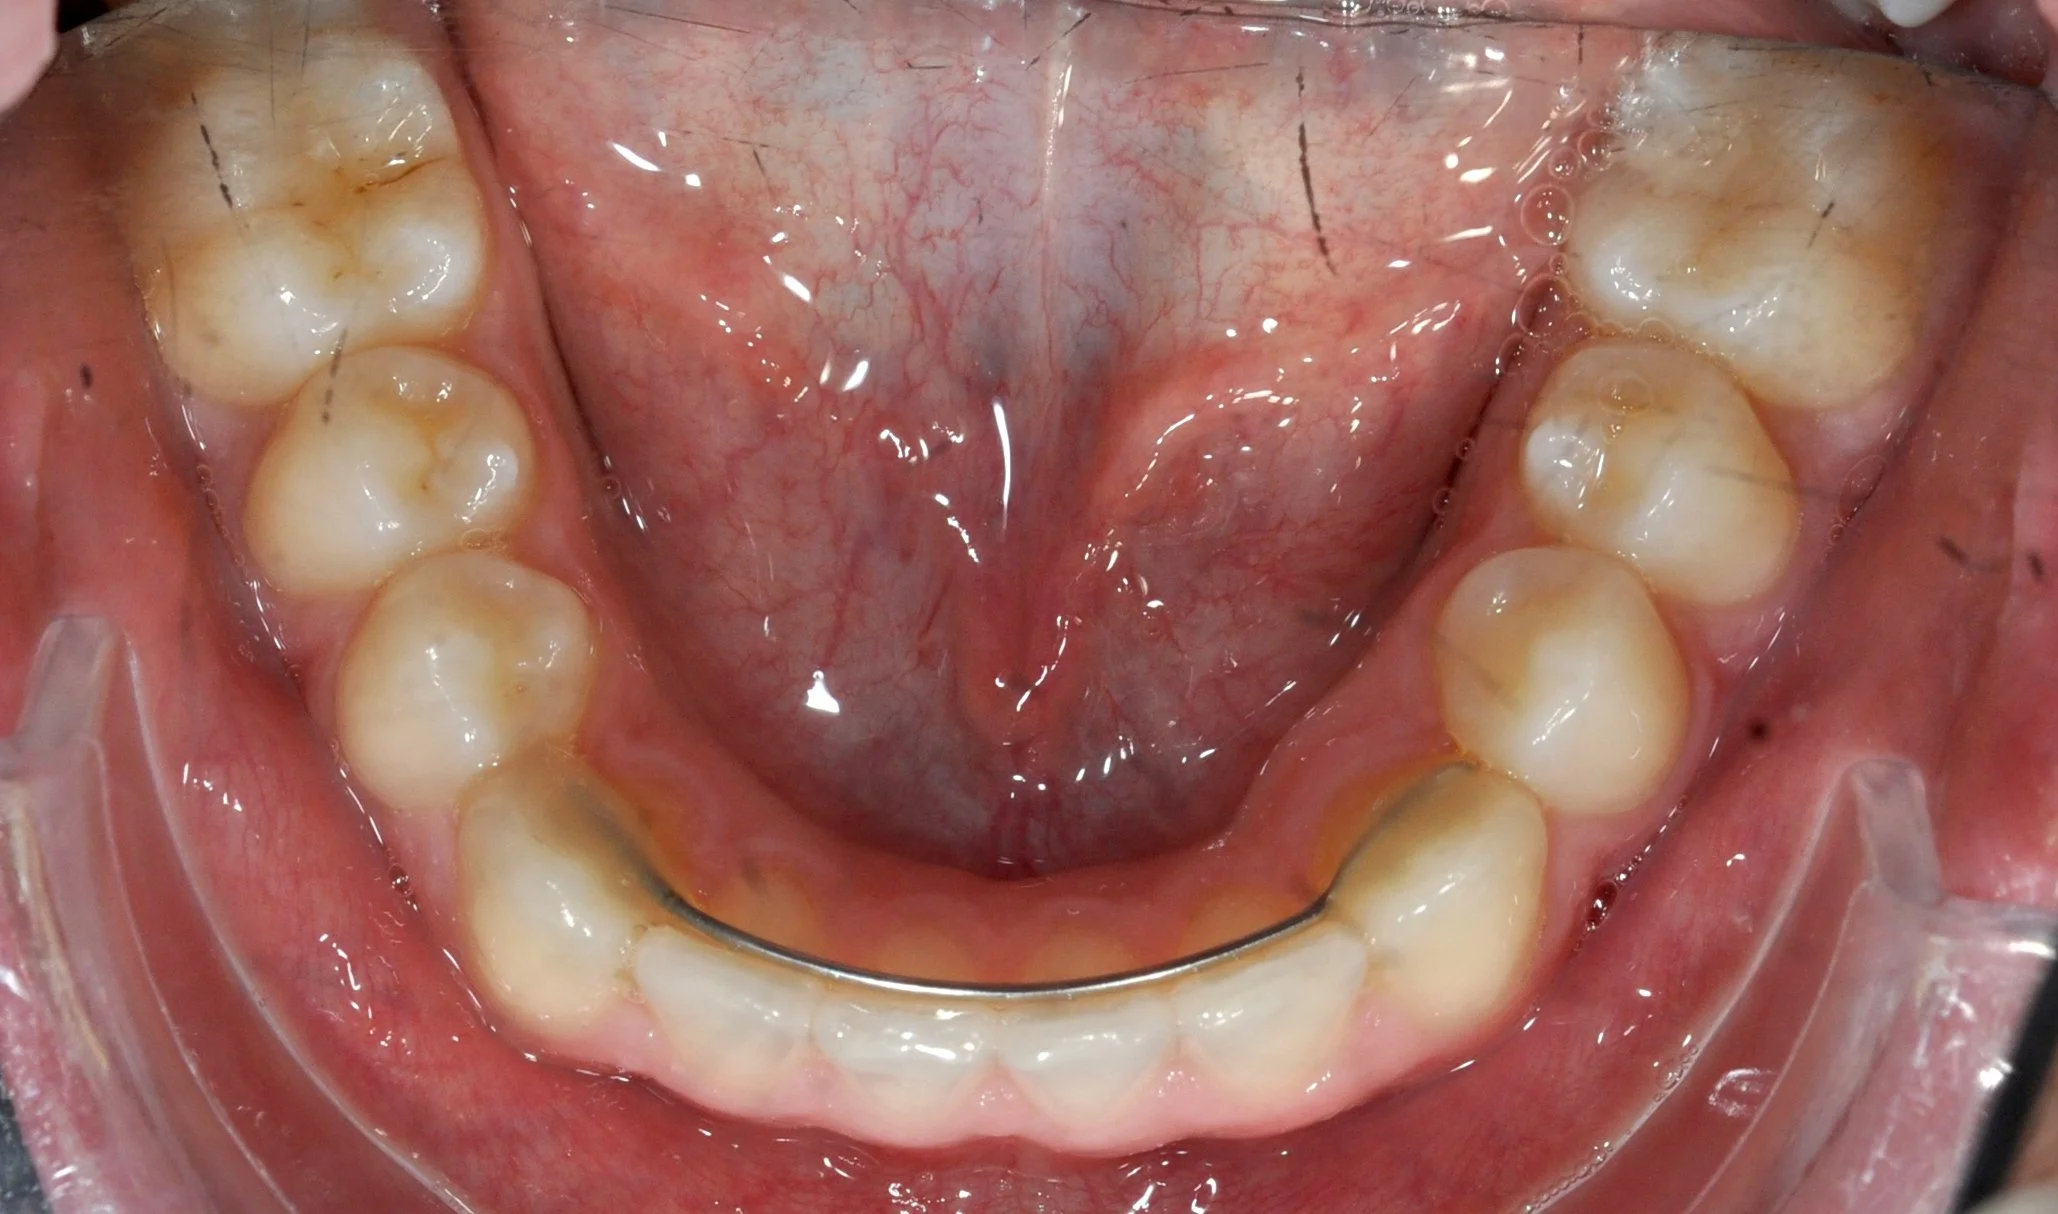

Caso 2 – Allineatori trasparenti in paziente adulto

Paziente adulto con importante affollamento dei denti inferiori, arcate strette e tendenza al morso aperto, con difficoltà nel corretto contatto tra i denti superiori e inferiori.

PRIMA